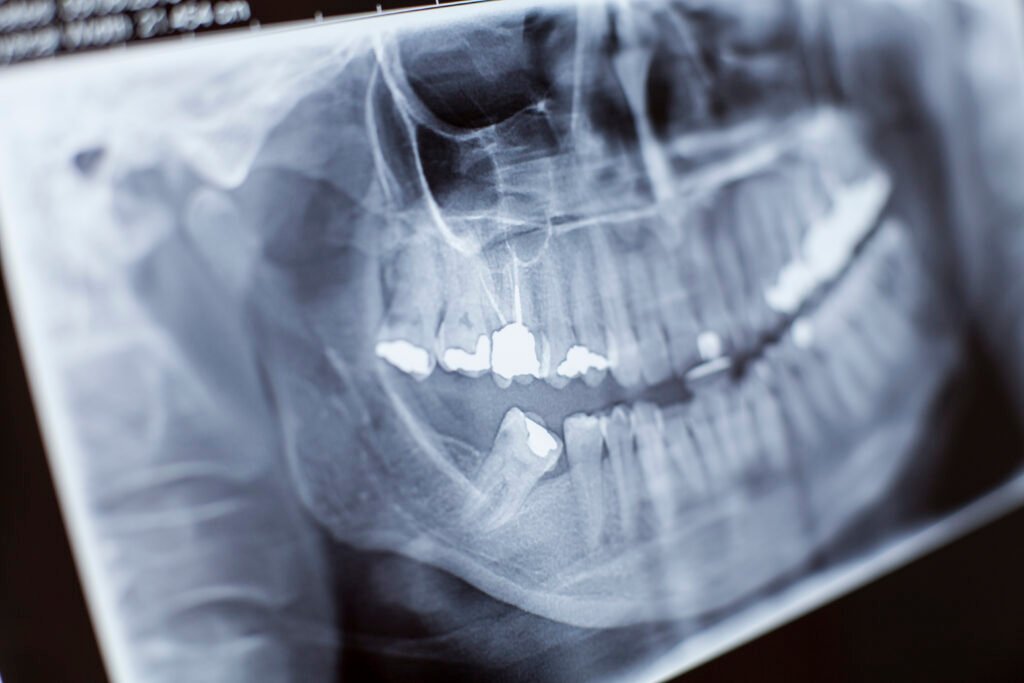

Radiografía dental y seguridad: dosis, cuándo se usa y por qué es necesaria

Radiografía dental: por qué sigue siendo tan importante La radiografía dental permite ver lo que no se aprecia a simple vista: caries entre dientes, infecciones en la raíz, pérdida de hueso por enfermedad periodontal, posición real de las muelas del juicio o el hueso disponible para un implante. Por eso es una herramienta clave para […]